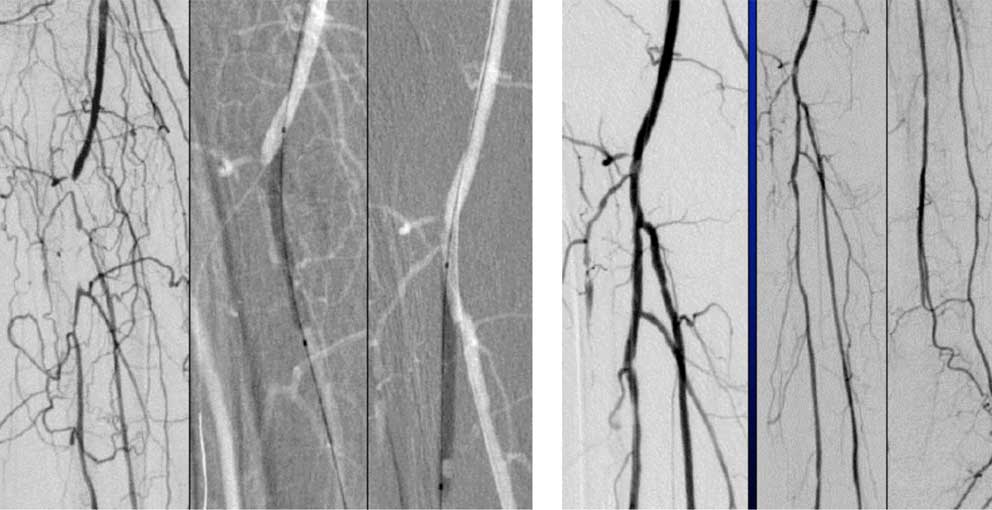

Verschlossene rechte Oberschenkelschlagader (Arteria femoralis) vor und nach PTA mit Stentimplantation.